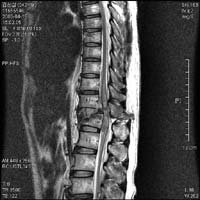

<Ç㸮µð½ºÅ©>

<¼ö¼úÀü>

<¼ö¼úÈÄ>

Á¦

4.5¹ø ¿äÃߺΠÃß°£ÆÇ Å»ÃâÁõÀ¸·Î ¼ö¼úÇÑ

ȯÀÚÀÇ ¿äÃß MRI¼Ò°ßÀ¸·Î ¼ö¼úÈÄ Å»Ãâ

µð½ºÅ©ÀÇ Á¦°ÅµÈ ¸ð½À°ú ÀûÃâµÈ µð½ºÅ©¸¦

º¼ ¼ö ÀÖ´Ù.